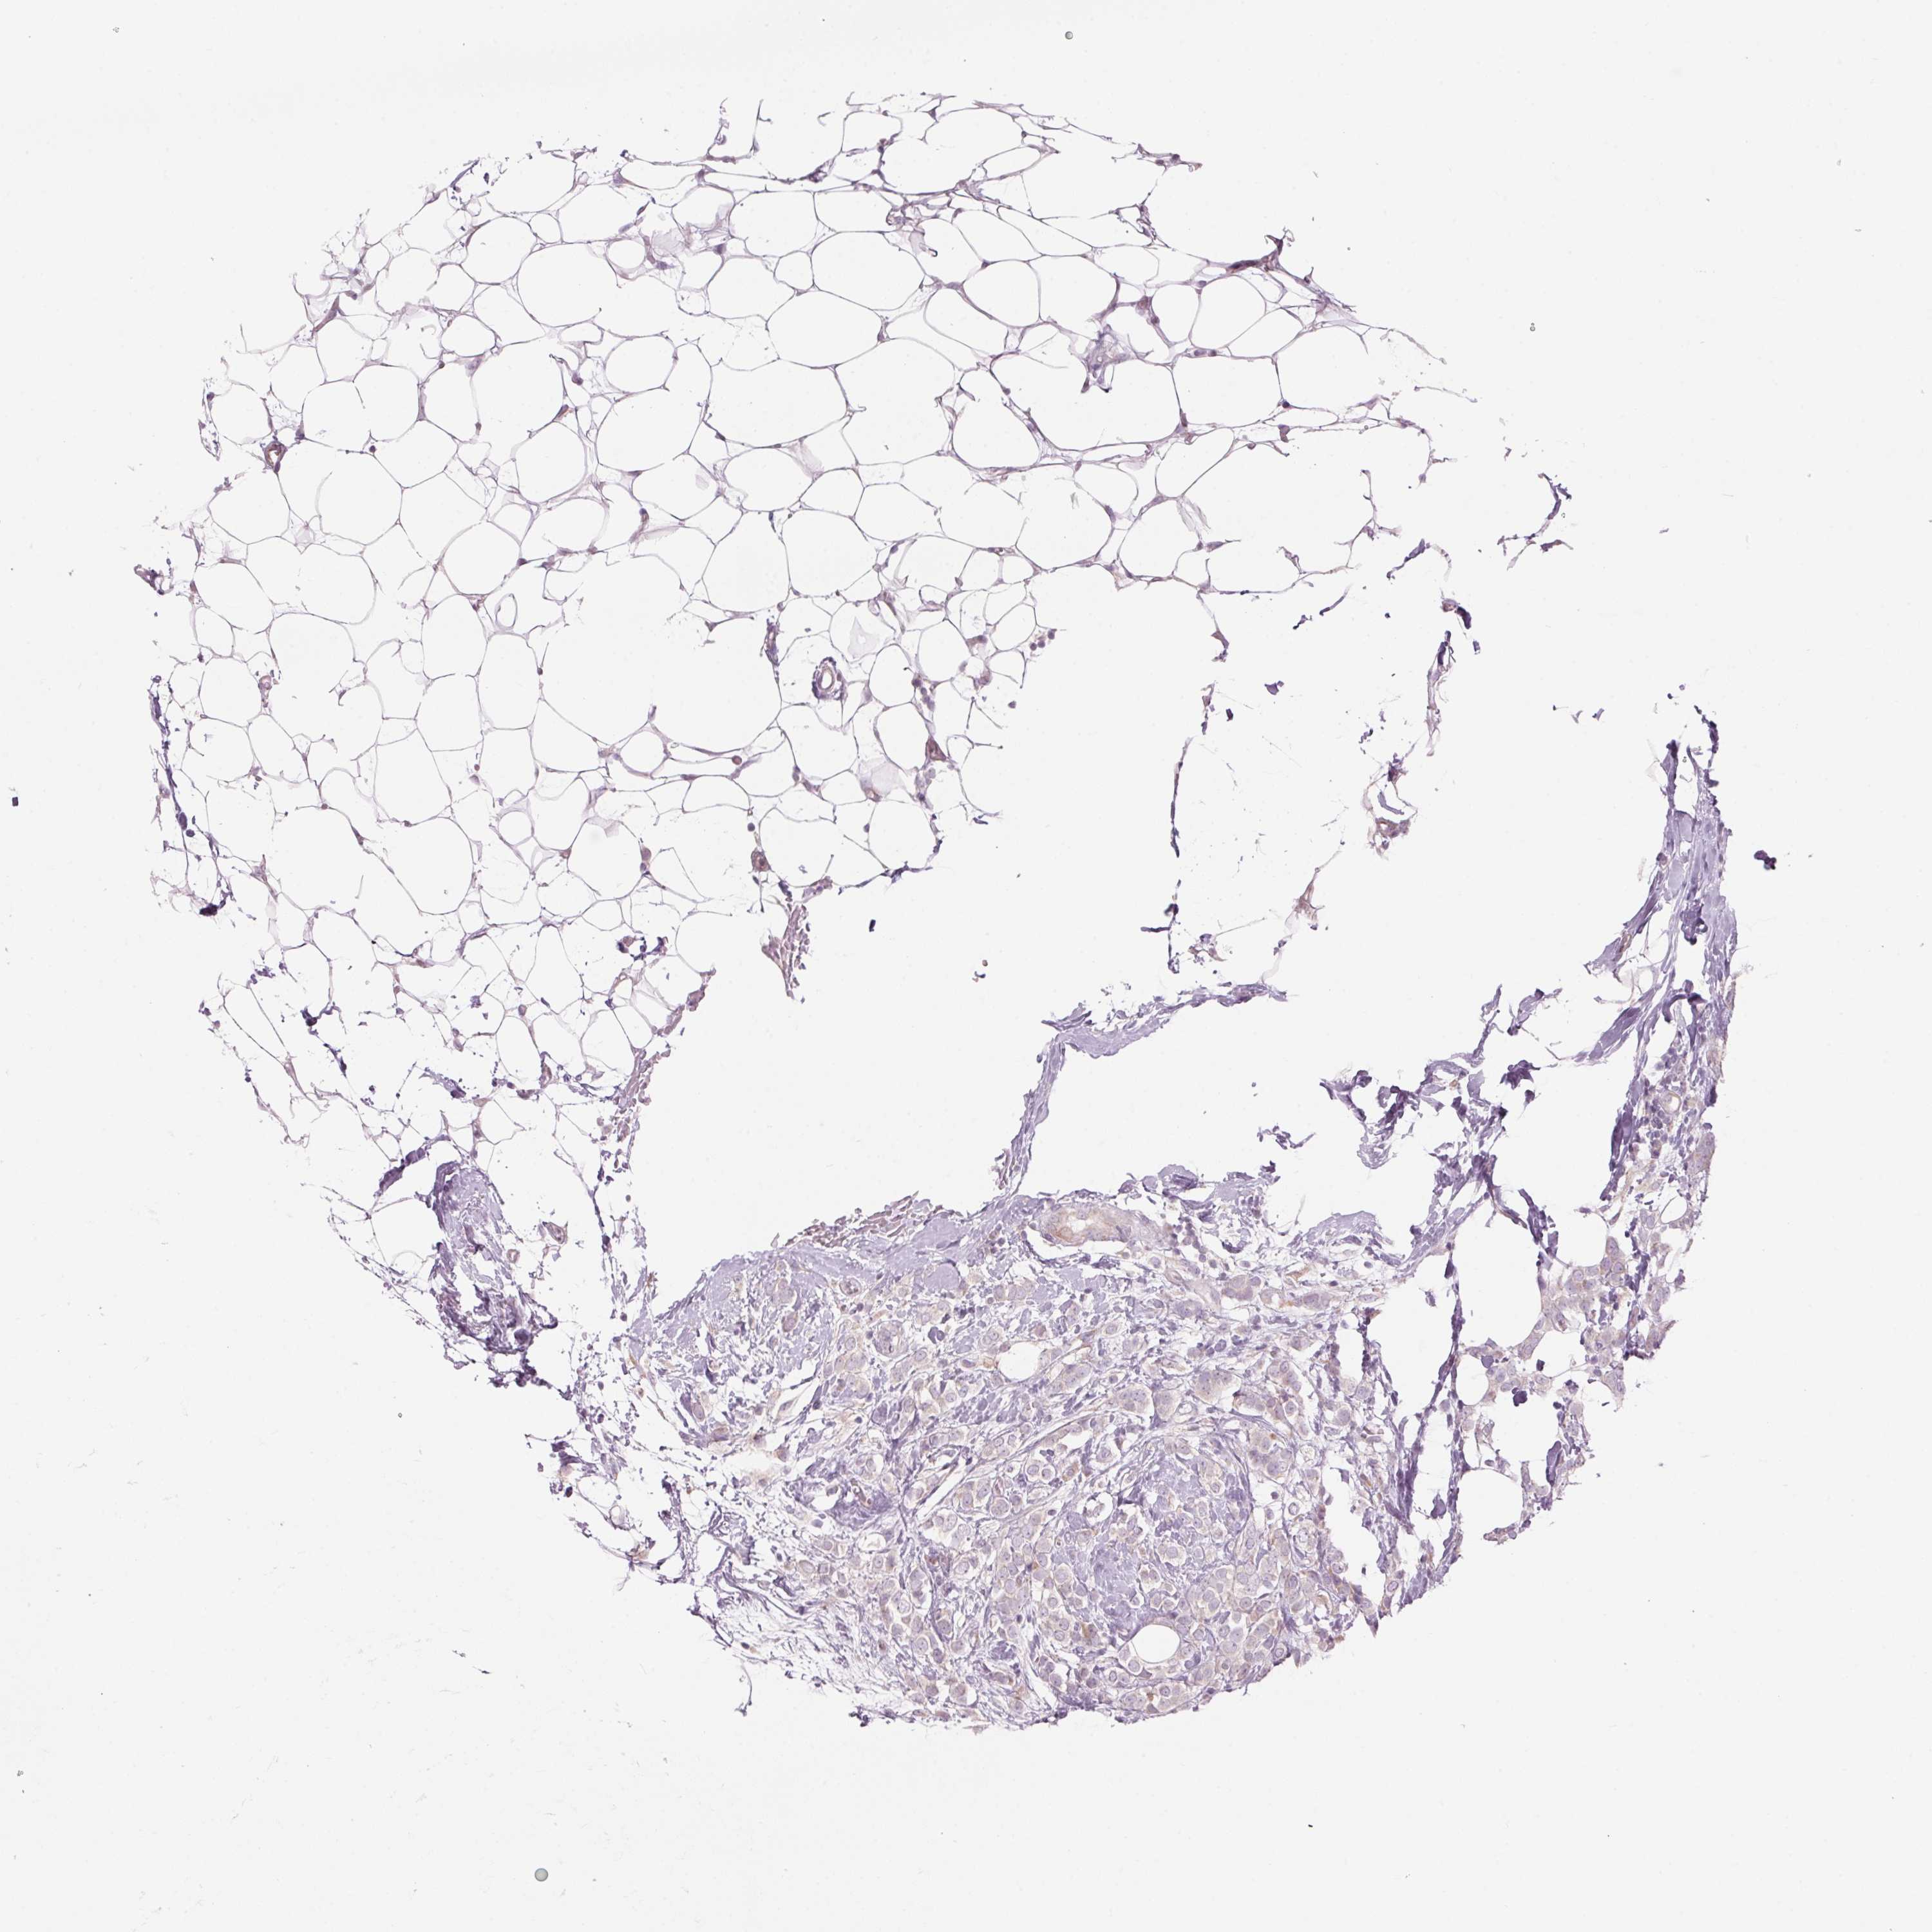

CANCER BREAST CANCER Show tissue menu

BRCA TCGA BRCA VALIDATION PROTEIN EXPRESSION

ANTIBODIES

AND

VALIDATION